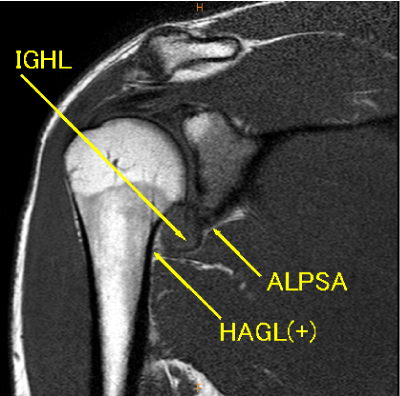

MRI所見

MRIから前方脱臼が示唆された症例。問診票から腕相撲による外傷があることがわかる。

骨性Bankart lesion, 骨片, HAGL, 後方関節唇損傷